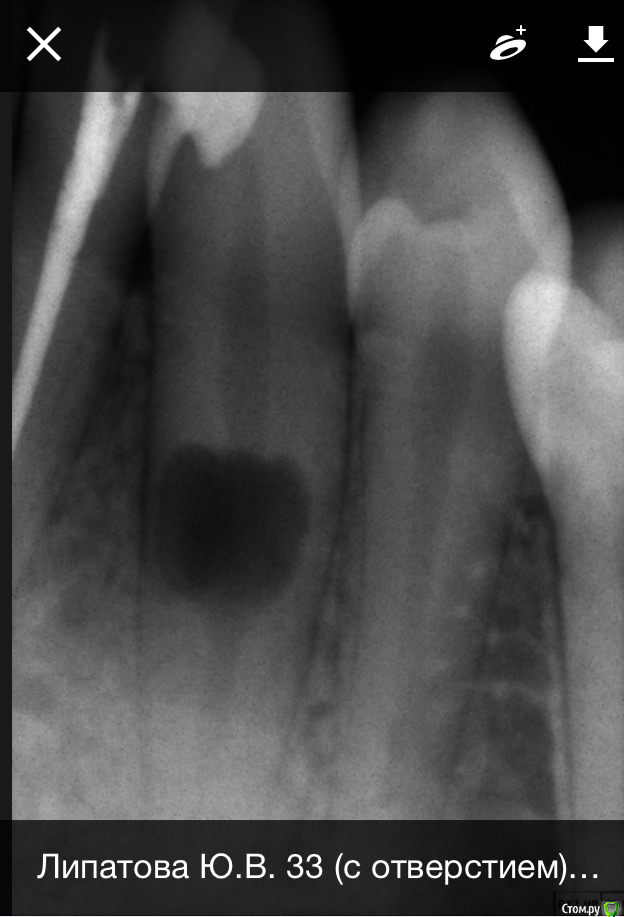

Юл1. Опубликовано 14 февраля, 2020 Поделиться Опубликовано 14 февраля, 2020 Здравствуйте, ситуация такая: 14. 02 пришла лечить 32 зуб, и случайно на снимке обнаружили это. Я была у двух опытных врачей, никто с таким не сталкивался. Мнения расходятся, один доктор говорит удалять, второй не трогать, по возможности сделать кт и наблюдать, делать снимки два раза в год. Я бы удалила, но нет финансовой возможности ставить имплант. Подскажите как быть? Возраст 26 лет, лет 5 назад делала снимок панорамный, зуб был в порядке, травм не было. Ссылка на комментарий

Дмитрий Л. Опубликовано 14 февраля, 2020 Поделиться Опубликовано 14 февраля, 2020 (изменено) Имплант там не особо и встаёт. https://bestendoglenview.com/wp-content/uploads/2012/04/Internal-inflammatory-root-resorption-the-unknown-resorption-of-the-tooth.pdf С рентгеном раз в полгода можно и влипнуть. Если решите наблюдать, то сначала раз в две недели 2 раза, потом раз в 4 недели полгода. Иногда внутрення резорбция корня случается сама по себе (по непонятным науке причинам), но иногда есть пусковые факторы. Кариес-пульпит или травма, в т.ч. окклюзионная (из-за прикуса или бруксизма). Я рекомендую вам обратиться к ХОРОШЕМУ эндодонту и пролечить зуб. Это, конечно же, может вызвать и обострение, и осложнение, но шанс ещё есть и нужно его использовать. По-этому можете ждать пока оно рассосётся или разболится, а можете пытаться спасти. Не отчаивайтесь. В крайнем случае хирурги с нашего форума смогут забрать нижнюю часть зуба, а верхнюю оставить. Успехов! Изменено 14 февраля, 2020 пользователем Дмитрий Л. 1 Ссылка на комментарий